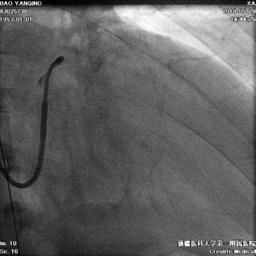

冠状静脉造影

● 十极标测电极进入窦口后总是超选小分支,进入过程中逆向旋转十极标测电极,顺利避开小分支开口,进入主干,造影显示可用后静脉和侧静脉各一个

鞘中鞘超选靶血管

● 使用鞘中鞘超选入靶血管造影,明确靶血管远端情况。